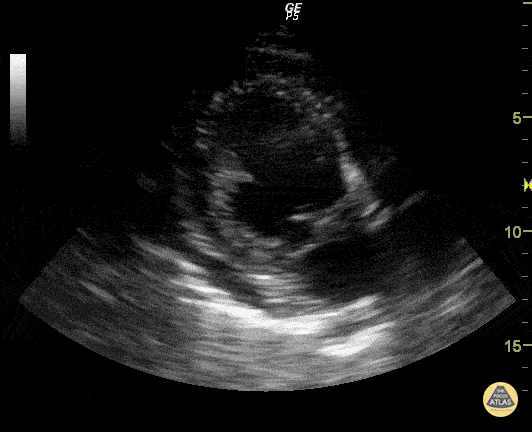

https://www.thepocusatlas.com/valvulopathy

View: Unspecified Parasternal Long Axis Parasternal Short Axis Apical Four-Chamber Subcostal Four-Chamber Subcostal Inferior Vena Cava Right Upper Quadrant Left Upper Quadrant Suprapubic Longitudinal Suprapubic Transverse Subxiphoid Anterior Thoracic Phrenic